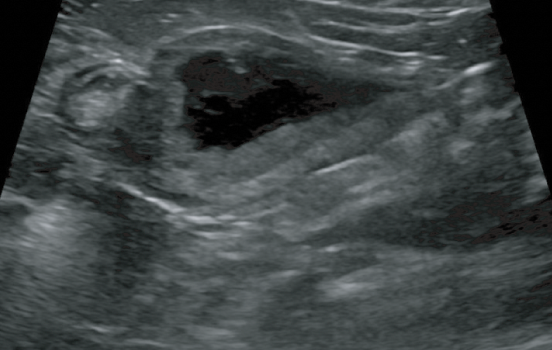

본원에서는 혈액검사를 비롯한 초음파 검사, 방사선 촬영, 내시경 검사 등을 통한 진단을 실시하고 있습니다.